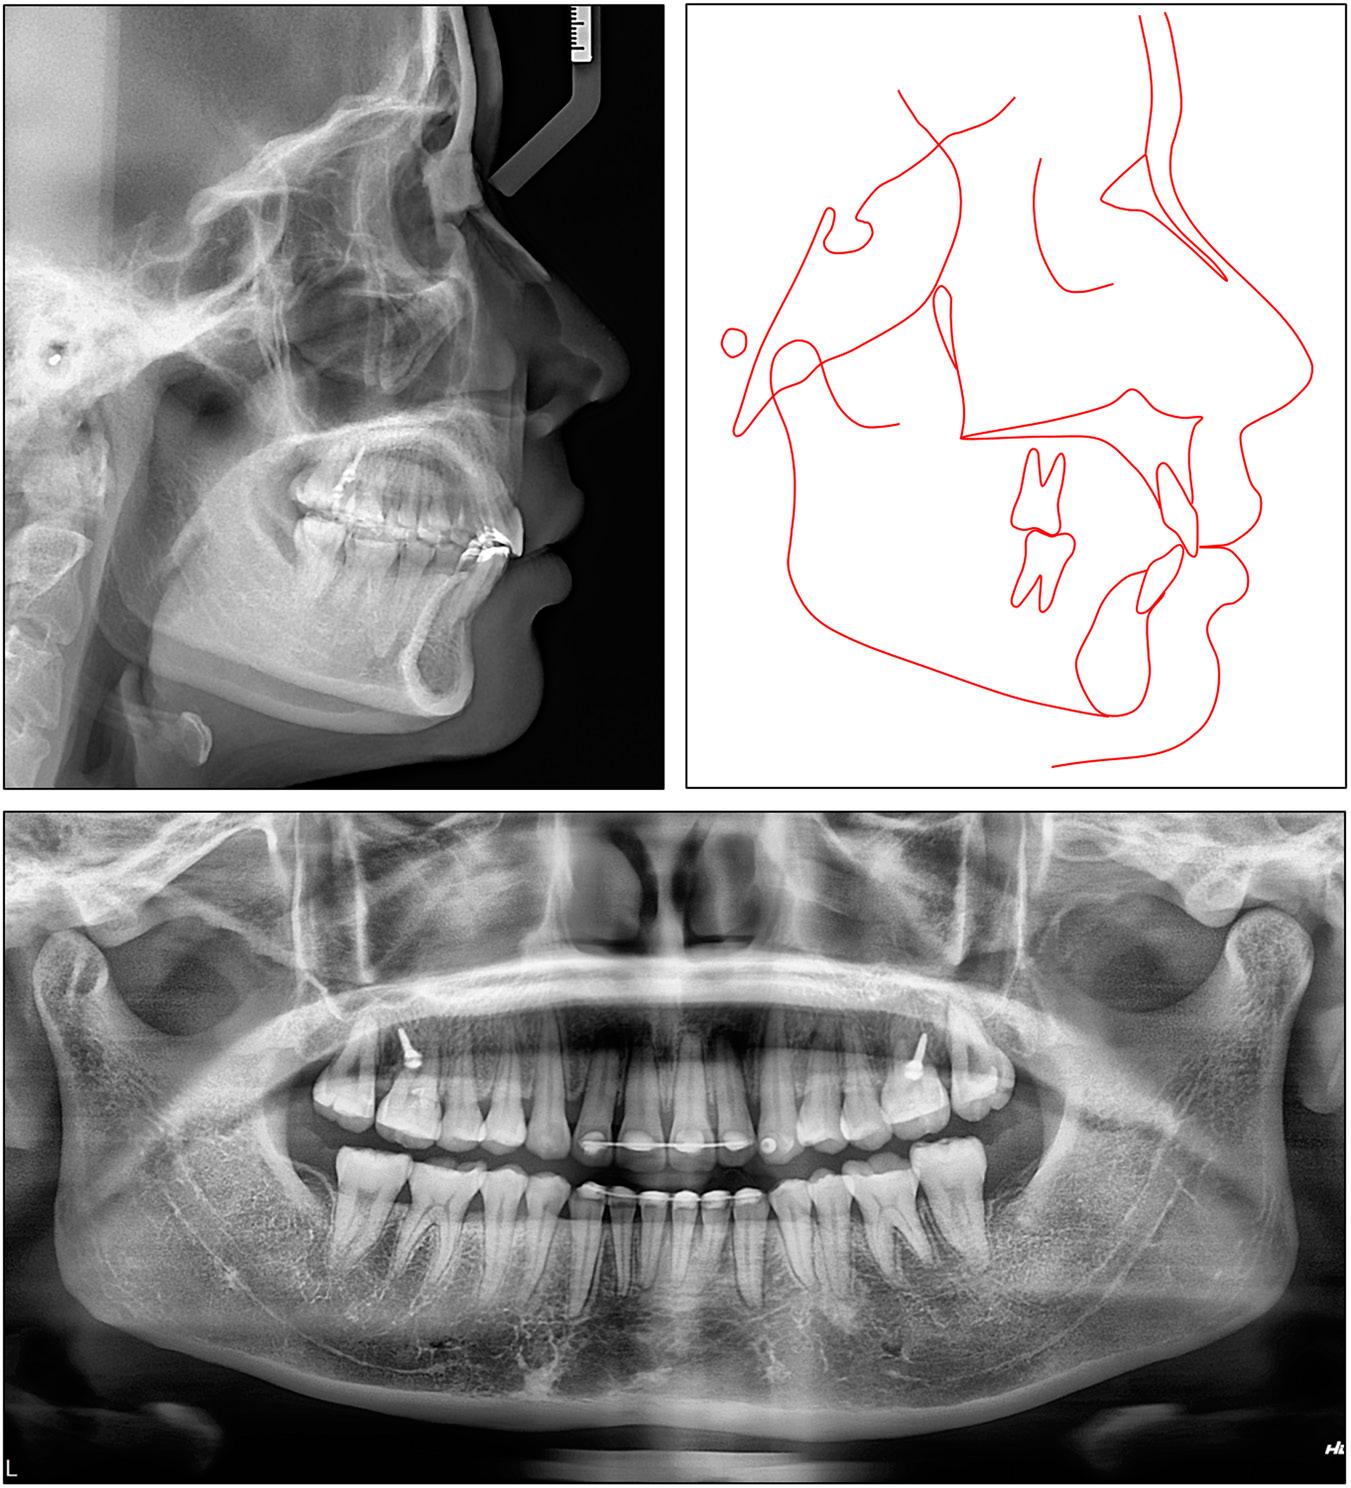

From the frontal view, the patient exhibited well- balanced facial proportions and her mandible deviated to the left (Figure 9). The lateral view showed a convex profile with a normal nasolabial angle and protruded maxilla. The posed smile revealed an excessive gingival exposure of 2 mm. No signs of a temporomandibular disorder were detected.

Case 2: initial extraoral and intraoral photographs.

On intraoral examination, the patient presented full-cusp Class II molar and canine relationships on the left side and end-on Class II canine and Class I molar relationships on the right side. The transverse dimensions of both the upper and lower arches fell within the normal range. There was moderate crowding of 4.5 mm and 4.0 mm in the upper and lower arch, respectively. The lower curve of Spee was accentuated and the upper occlusal curve was reversed with retroclined and extruded upper central incisors and labially displaced upper lateral incisors. The upper and lower left second molars were in a scissor bite. The upper dental midline was centered with the facial midline, but the lower dental midline deviated 1.5 mm to the left.

The cephalometric analysis showed a skeletal Class II relationship with a slightly retruded mandible and a protruded maxilla (SNA: 85.5°, SNB: 75.8°, ANB: 9.7°). The vertical skeletal pattern indicated a slight hypodivergence (FMA: 21.4°). The upper incisors were excessively retroclined (U1/SN: 73.9°) while the lower incisors were proclined (IMPA: 103.4°). The upper incisal display was slightly increased (3.7 mm). The upper lip was slightly protruded but the lower lip was normally placed (upper lip to E-line, 1.9 mm; lower lip to E-line, 0.2 mm) (Table II). The panoramic radiograph indicated the presence of all teeth, excluding the mandibular left third molar (Figure 10).

Case 2: initial panoramic and cephalometric radiographs and tracing.